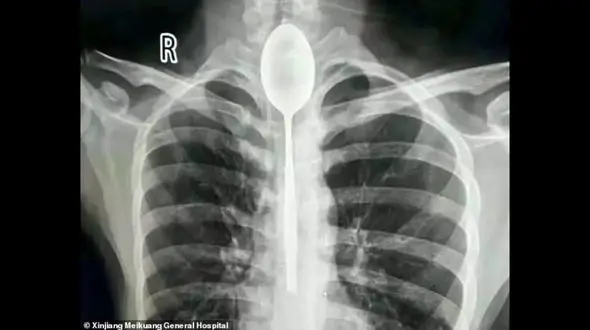

حوادث رکنا: یک مرد چینی قاشقی را قورت داد و قاشق یک سال در گلوی او بود.